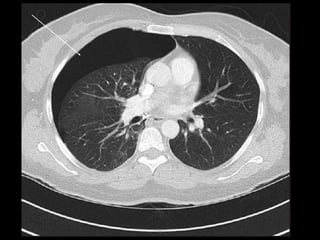

Chest CT scan :-

• Intrapleural gas along with loculated pneumothoraces.

• Pleural effusion, pneumothorax.

RADIOLOGICAL FINDINGS Chest X-ray:- • Hyper translucency between the lung & thoracic cage. • Razor sharp border of the collapsed lung. • Shifting of mediastinum on the opposite side of injury. Chest CT scan :- • Intrapleural gas along with loculated pneumothoraces. • Pleural effusion, pneumothorax. Chest Ultrasound :- • Smooth horizontal echogenic lines are seen above and below the pleural lines. • Absence of lung sliding and B - lines.